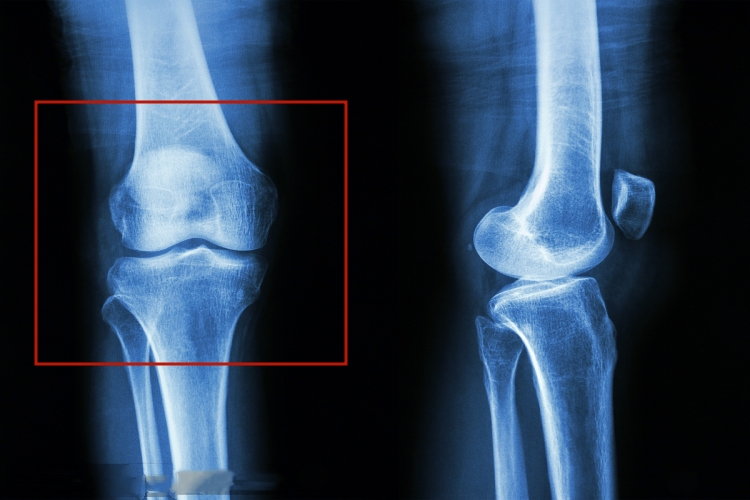

膝关节由股骨与小腿的胫骨和腓骨以及髌骨构成,胫骨居小腿内侧,属粗大长骨,为小腿主要承重骨,与之相邻的骨为腓骨。

胫骨分一体两端,上端膨大,向两侧突出,形成内侧踝和外侧踝;两踝上面各有上关节面,与股骨踝相关节;两上关节面之间的粗糙小隆起,称髁间隆起;外侧髁后下方有腓关节面与腓骨头相关节;上端前面的隆起称胫骨粗隆,内外侧和胫骨粗隆于体表均可扪到,胫骨呈三棱柱形,较锐的前缘和平滑的内侧面直接位于皮下,外侧缘有小腿骨间膜附着,称骨间缘。

后面有斜向下内的比目鱼肌线,体上、中1/3交界处附近,有向上开口的滋养孔,胫骨下端稍膨大,其内下方的凸起称内踝,下端的下面和内踝的外侧面有关节面与距骨相关节,下端的外侧面有腓切迹与腓骨相接。